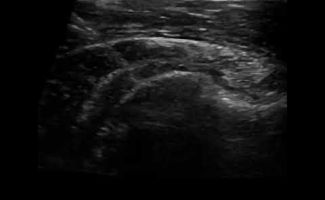

Παρότι η αρχική διάγνωση της Ασβεστοποιού Τενοντίτιδας μπορεί να γίνει και με απλή ακτινογραφία ώμου, το Υπερηχογράφημα είναι η ενδεδειγμένη μέθοδος απεικόνισης των ασβεστώσεων, καθώς παρέχει λεπτομερείς πληροφορίες για το μέγεθος, τη θέση τους και το στάδιο στο οποίο βρίσκονται.

Όταν οι ασβεστώσεις βρίσκονται στο στάδιο της ρευστοποίησης μπορούν να απεικονιστούν υπερηχογραφικά, αλλά να μην απεικονιστούν στην απλή ακτινογραφία. Επιπλέον, το Υπερηχογράφημα παρέχει τη δυνατότητα μελέτης των τενόντων ώστε να διαπιστωθεί αν συνυπάρχει άλλο πρόβλημα, όπως ρήξη του τένοντα.